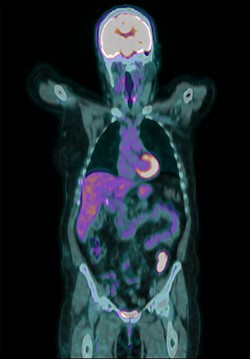

Surveillance colonoscopy in 2018 identified a fungating nonobstructing mass in the sigmoid colon (Fig. 1). Histology from a biopsy showed poorly differentiated carcinoma (Fig. 2). Given the history of breast cancer, further immunohistochemical staining was performed, which was positive for E-cadherin (Fig. 3), ER (Fig. 4), PR, GATA3 binding protein (GATA 3) (Fig. 5) and negative for Cytokeratin 20 (CK20) (Fig. 6). This confirmed metastatic invasive ductal carcinoma of breast. A positron emission tomography (PET) scan showed only the retroperitoneal mass involving the proximal sigmoid colon with no other evidence of metastatic disease (Fig. 7).

PET scan showed only the retroperitoneal mass involving the proximal sigmoid colon with no other evidence of metastatic disease.